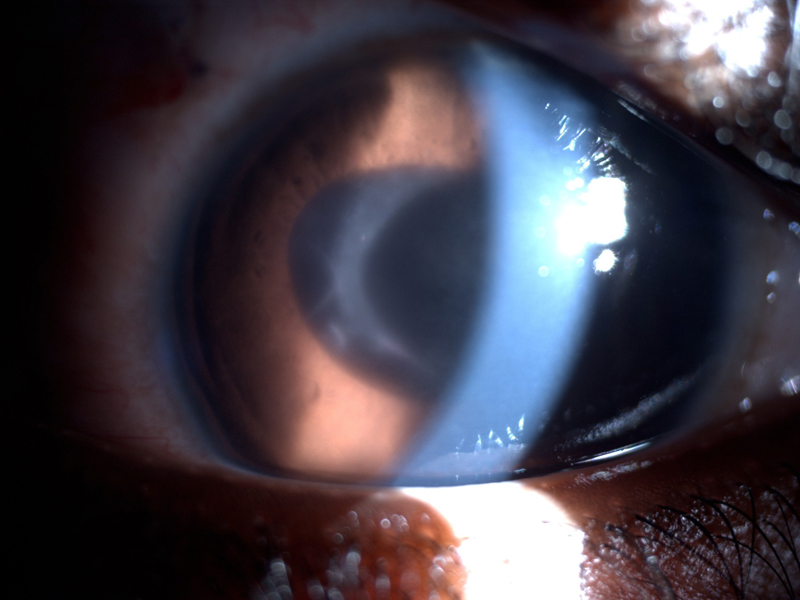

7. Las principales complicaciones del uso de lentes intraoculares son la aparición de membranas ciclíticas, sinequias posteriores y depósitos celulares sobre la lente que pueden obligar a explantar la misma (

Figura 2).

Figura 2. Niño de 9 años con uveítis crónica idiopática bilateral intervenido a los 7 años en otro país mediante facoemulsificación + implante de lente. Presenta queratopatía en banda, fibrosis preLIO, membrana ciclítica e hipotonía severa.